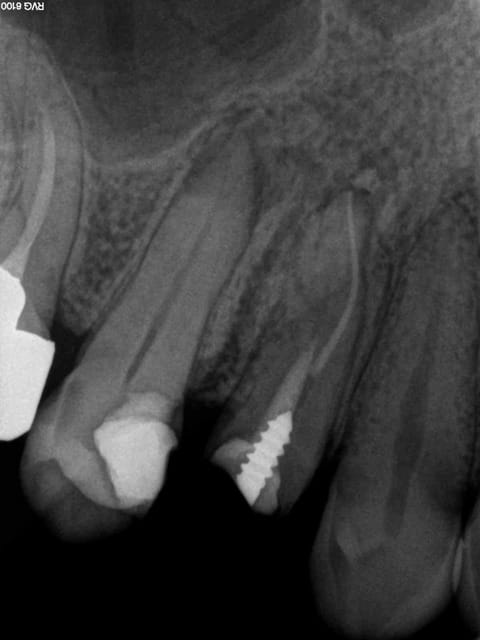

Post de depart !

Honnêtement, la dent est quand même bien niquée !

Fêlure mesiale et distale, le curetage n'est pas complet sur l'arrête restante.

Une couronne, c'est pas une connerie, patient 25-35 on tente l'onlay, patient 45-55, je couronne directement !

C'est une 6 ! 150 kg pression au cm2 !

adhésion 30 mPA = 300Kg au Cm² ...

Tenon dans une racine avec les KG ?

Combien de temps tu garanties l'étanchéité sous la couronne ?....

La meilleure endo c'est la pulpe

La couronne sur une dent vivante dans ce cas précis, ne me semble pas un mauvais choix.... Vaut mieux une couronne bien adaptée sur dent vivante, qu'un onlay mal collé...

Par contre quel intérêt de dépulper ? Si c'est pour que ça coûte rien au patient parce qu'on fait un IC à 350€ ... je comprends vraiment pas !